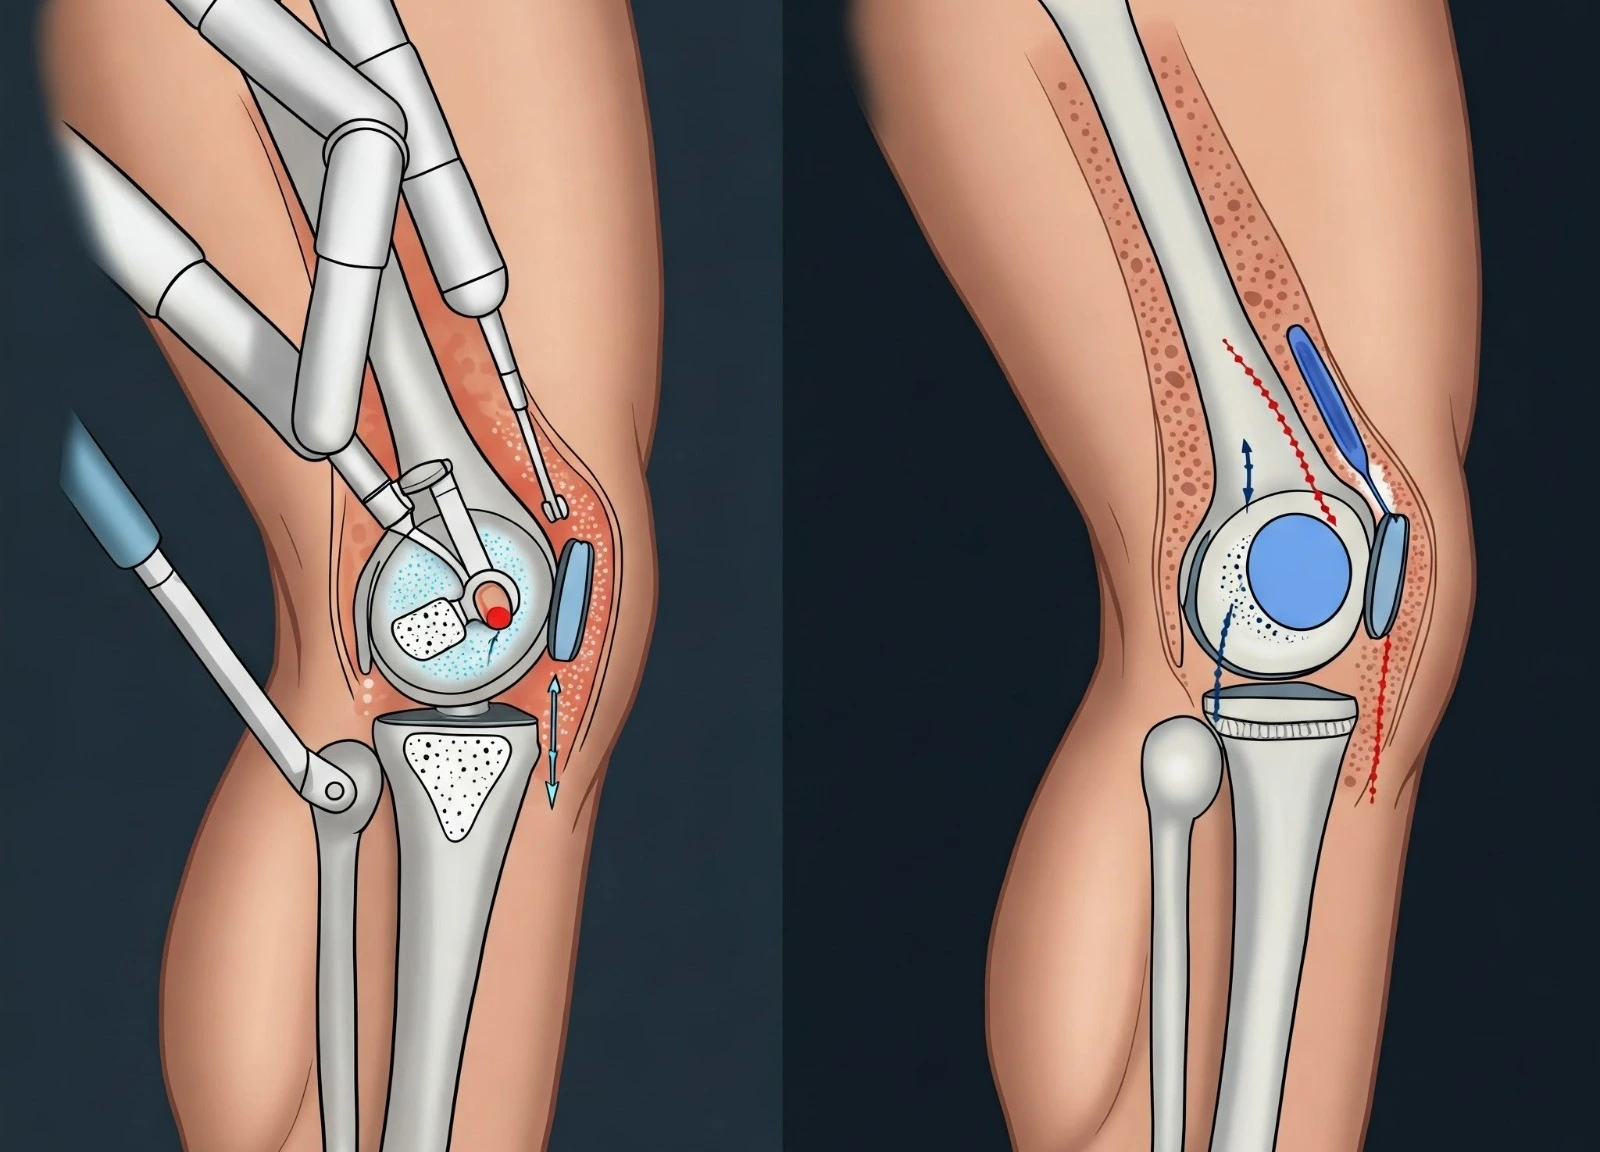

He has completed MBBS, MS [ORTHOPAEDICS], DNB [ORTHOPAEDICS], FIJR, FIAS, FIAT followed by specialized fellowships in Advanced Trauma, Robotic & Conventional Joint Replacement, and Arthroscopy. His clinical expertise spans adult and pediatric trauma, fracture management, joint replacement surgeries, sports injuries, and spine-related conditions.

Dr. Anmol has treated 2000+ patients and has been involved in 500+ orthopaedic surgeries, including complex trauma cases and advanced joint replacement procedures. His exposure to robotic joint replacement and arthroscopy allows him to offer precise, minimally invasive solutions with faster recovery and improved outcomes.